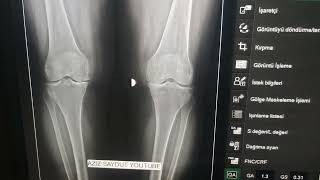

Diz Grafik Radyoloji Anatomik Anlatım. Kenn